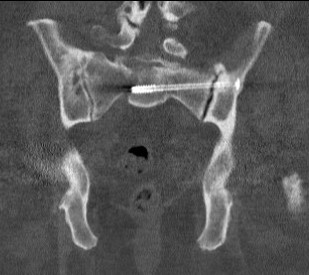

Sacro-iliac screws

Technique

Radiolucent table with image intensifier

- 45o cephalad and caudal / inlet and outlet views

Must reduce SI joint

- reduce vertically with traction on limb / outlet view

- reduce AP usually via anterior plate or external fixation / inlet view

Guide wire insertion into body of S1

- anatomic safe zone

- between S1 foramen and superior ala on outlet view (outlet view)

- between neural canal and anterior body (inlet view)

Insert 6.5 mm partially threaded cannulated screw, to aid compression

Post operative

Check screw position with CT

Protected weight bear for six weeks